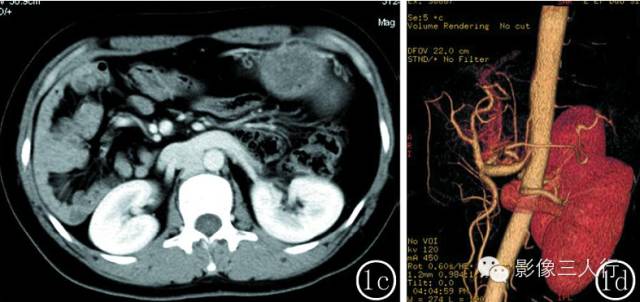

图 2 女性 , 52 岁 。 图 2a 水平肝 ,胃 、脾反位 ,均位于右季肋区 ,脾呈多个大小不等的结节 ,肝段下腔静脉缺如 ,奇静脉及半奇静脉异常增粗 。 图 2b冠脉位重建图像 :右侧季肋区可见 6 个大小不等的小脾脏 。 图 2c 胰腺反位 ,胰腺体尾部发育短小 ,胰腺周围可见渗出 ,双侧肾静脉回流入奇静脉